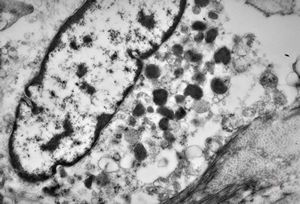

F,43y. | blood - leukemia - bacteriaemia - phagocytosed microbes

phagocytosed microbes

M,2w. | bacteriaemia - phagocytosed microbes

phagocytosed microbe